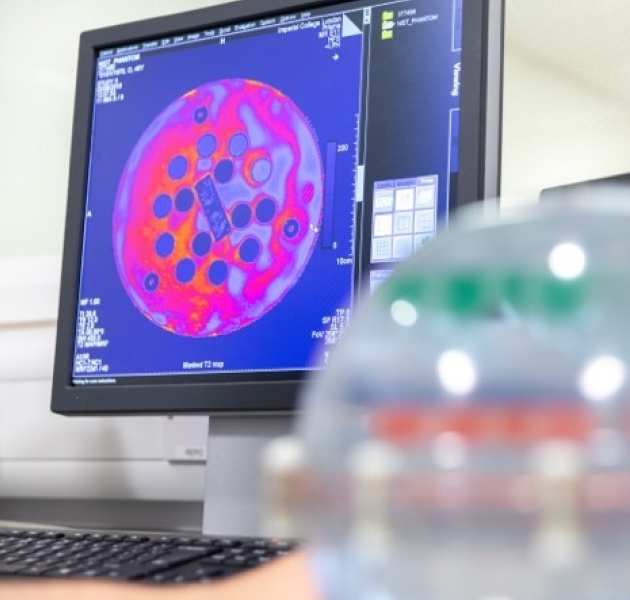

MR Fingerprinting

We are investigating MRF as a rapid and quantitative technique for characterising brain tumours.

We are investigating MRF as a rapid and quantitative technique for characterising brain tumours.